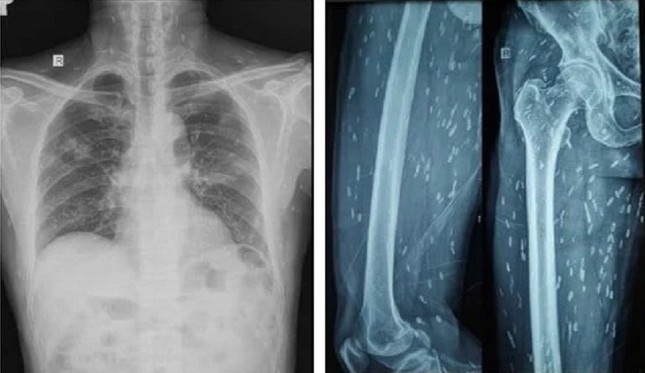

Trên kết quả X-quang và CT-Scan toàn thân, bác sĩ phát hiện bệnh nhân có vô số nang sán dải còn sống hoặc đã bị vôi hóa ở não, nhu mô phổi, trong da, cơ trên toàn bộ cơ thể. Qua điều tra dịch tễ, bác sĩ ghi nhận bệnh nhân có thói quen hay ăn gỏi thịt lợn tái sống và uống nước không đun sôi trong nhiều năm.

Ấu trùng nang sán dải lợn ký sinh khắp cơ thể người bệnh được phát hiện trên kết quả kiểm tra hình ảnh

Nang sán dải ký sinh ở bán cầu não hai bên là nguyên nhân khiến người bệnh bị tổn thương não, biểu hiện như đột quỵ